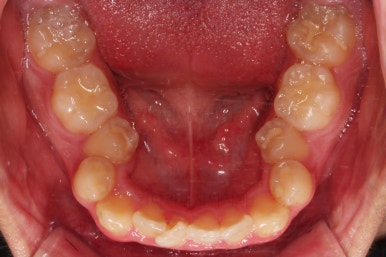

초진 시, 입안의 모습입니다.

치아를 모두 담기에 골격이 매우 작았어요.

이런 경우 치열이 ㅃ뚤어지거나 입이 튀어나오거나 뻐드렁니가 되거나 특정 치아가 묻혀버리거나 맨 뒤치아가 마치 사랑니처럼 올라오지 못한다거나 등등의 문제가 생기는데요.

이번 환자분은 전반적으로 삐뚠 상황이었어요.

앞니도 대칭적으로 삐뚤어져 흔히 나비치아라고 하는 형태로 보이고, 아랫니들은 U자 아치의 형태가 찌그러져 있네요.

당연히 교합도 맞지 않고요.